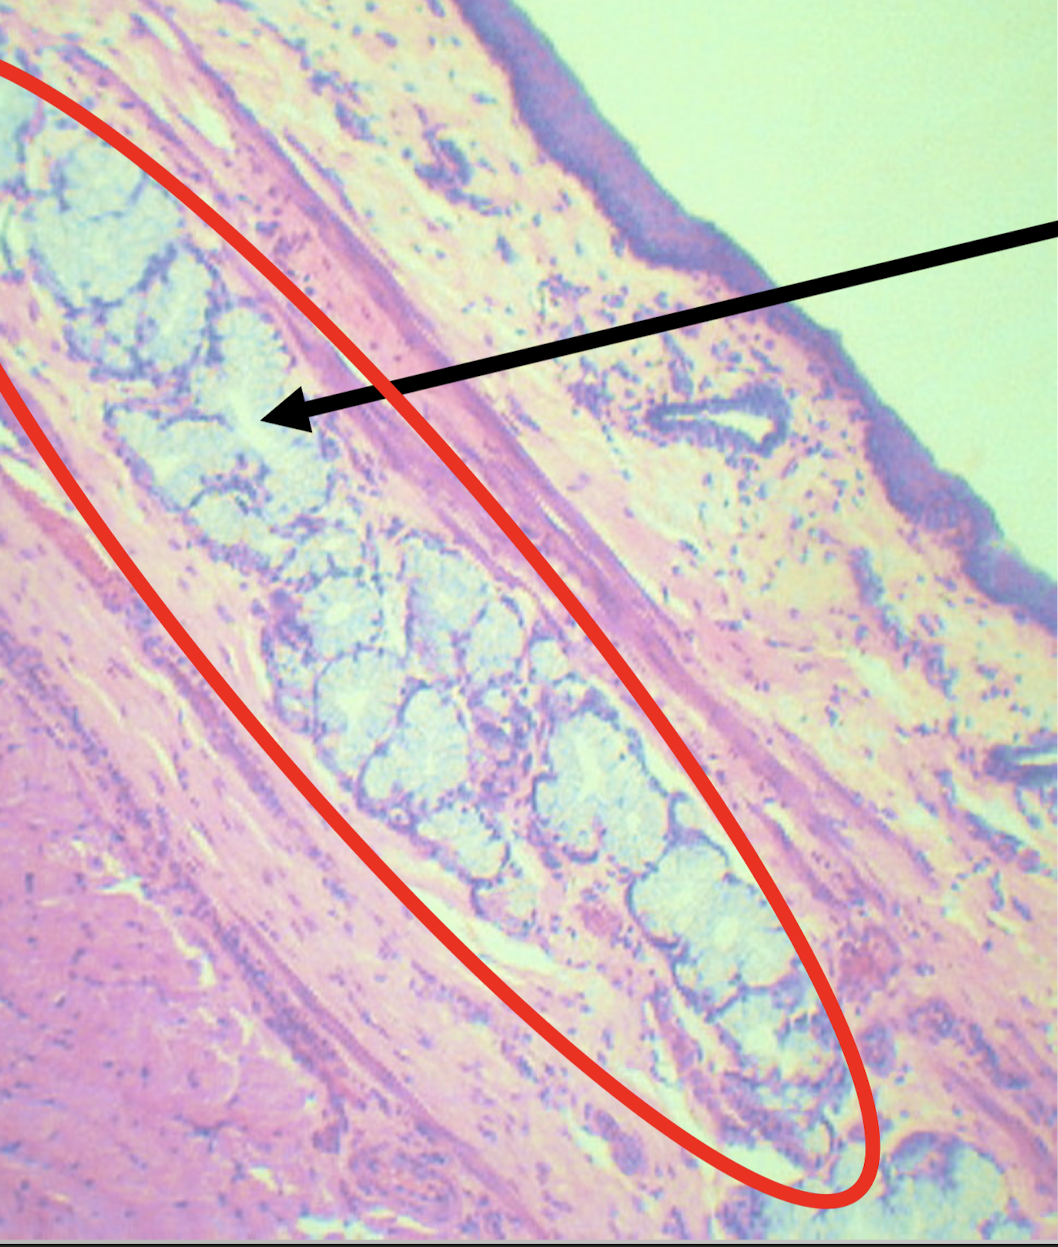

LPO - MUCOSA OF ESOPHAGUS

A: lining epithelium

B: lamina propria

C: muscularis mucosa

Identify the structure

Stratified squamous non-keratinized epithelium

Lining epithelium of the structure

Loose connective tissue with scattered lymphocytes; (+) superficial esophageal glands

Lamina propria of the structure

Morphology: branched coiled glands

Location: lower end of esophagus

MORPHOLOGY and location of lamina propria of structure

Single layer of smooth muscle

Muscularis mucosa of the structure